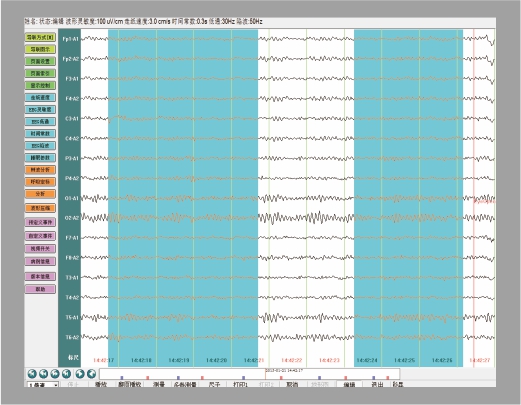

用戶便捷操作

導(dǎo)聯(lián)編輯 數(shù)據(jù)庫管理

支持單極、雙極、自定義任意導(dǎo)聯(lián)模式的編輯,滿足醫(yī)生不同的檢查方式; 病例數(shù)據(jù)庫分類管理,導(dǎo)入、導(dǎo)出數(shù)據(jù),方便病例存檔、備份;

阻抗測試 病例編輯

具有頭皮阻抗測試功能,通過觀察軟件指示燈,直觀判斷電極是否佩戴合適; 支持病例數(shù)據(jù)剪輯功能,便于醫(yī)生保存典型波形及教學(xué)備案;

多樣化測量\事件標(biāo)記

具有快捷測量、局部波形放大測量、波形卡尺測量等多種測量功能,滿足不同的數(shù)據(jù)測量需求采集病例時支持睜閉眼、深呼吸、閃光、聲刺激等多種事件誘發(fā)實驗。